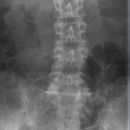

Lendenwirbelsäule a.- p.

Indikation

Fraktur und degenerative Veränderungen, Skoliose

Lagerung

Rückenlage, Arme auf Brust oder seitlich am Körper

Beine angewinkelt

Zentralstrahl

ZS senkrecht auf Objekt- und Detektormitte

Quer: 1-2 QF über oberen Beckenkamm

Bemerkung

möglichst bei Atemanhalten

auch im Stehen möglich (orthopädisch)

Gegenkontrolle: unteres Licht 2 QF über Symphysenrand

Qualitätskriterien

Scharfe und orthograde Abbildung aller Lendenwirbel mit ihren Querfortsätzen, der Kreuzdarmbeingelenke und des thorakolumbalen Überganges. Die Dornfortsätze sind mittelständig. Zwischenwirbelraum frei projiziert.